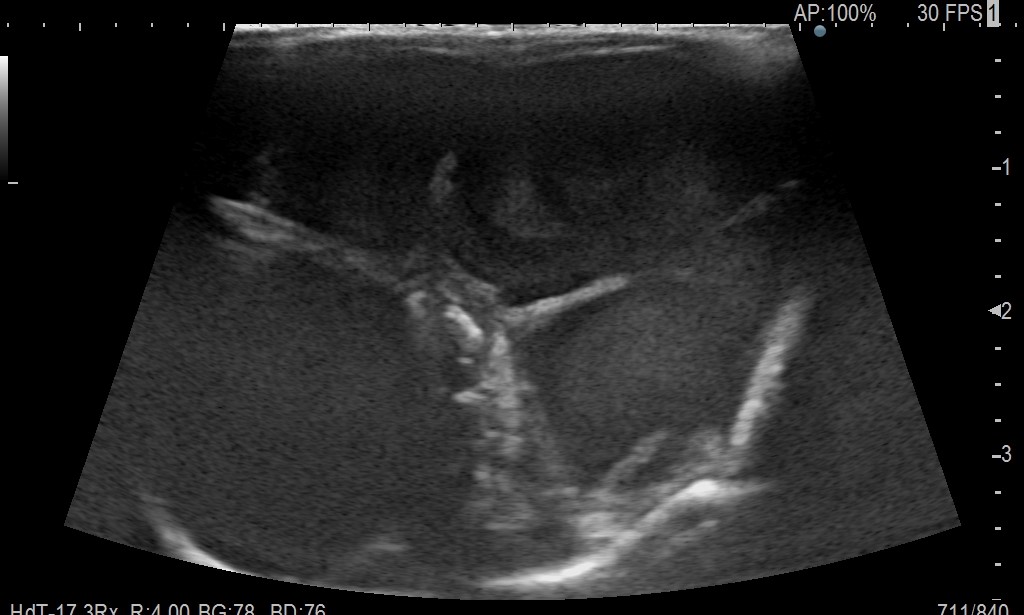

超音波検査画像:子宮内が腫れあがっている様子